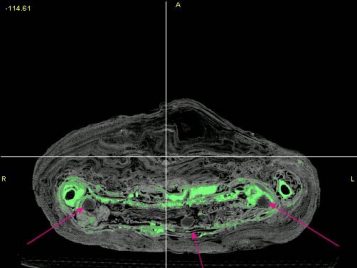

Now that I have the data, it is my responsibility to interpret it. I was fortunate enough to obtain powerful medical imaging software with a limited license and, with it, have started to build three-dimensional computer models. It is a surprisingly detailed process, and over the course of two weeks I have only been able to separate the legs and arms. Hopefully, within the bounds of my temporary software license I will be able to build an accurate representation of the skull and as much of the body as possible. These data sets will be saved in a format known as stereolithography (STL) data.

From these data, I will attempt to build accurate plastic representations of my computer models in what is known as a stereolithographic apparatus, or SLA. Under the guidance of Dr. Halloran, a model accurate to 13 nanometers should be producible. This model should provide scientists an accurate view of the child’s bones. From it, we will be able to study diet, age, and countless other aspects of the child’s life—all without ever touching the mummy.